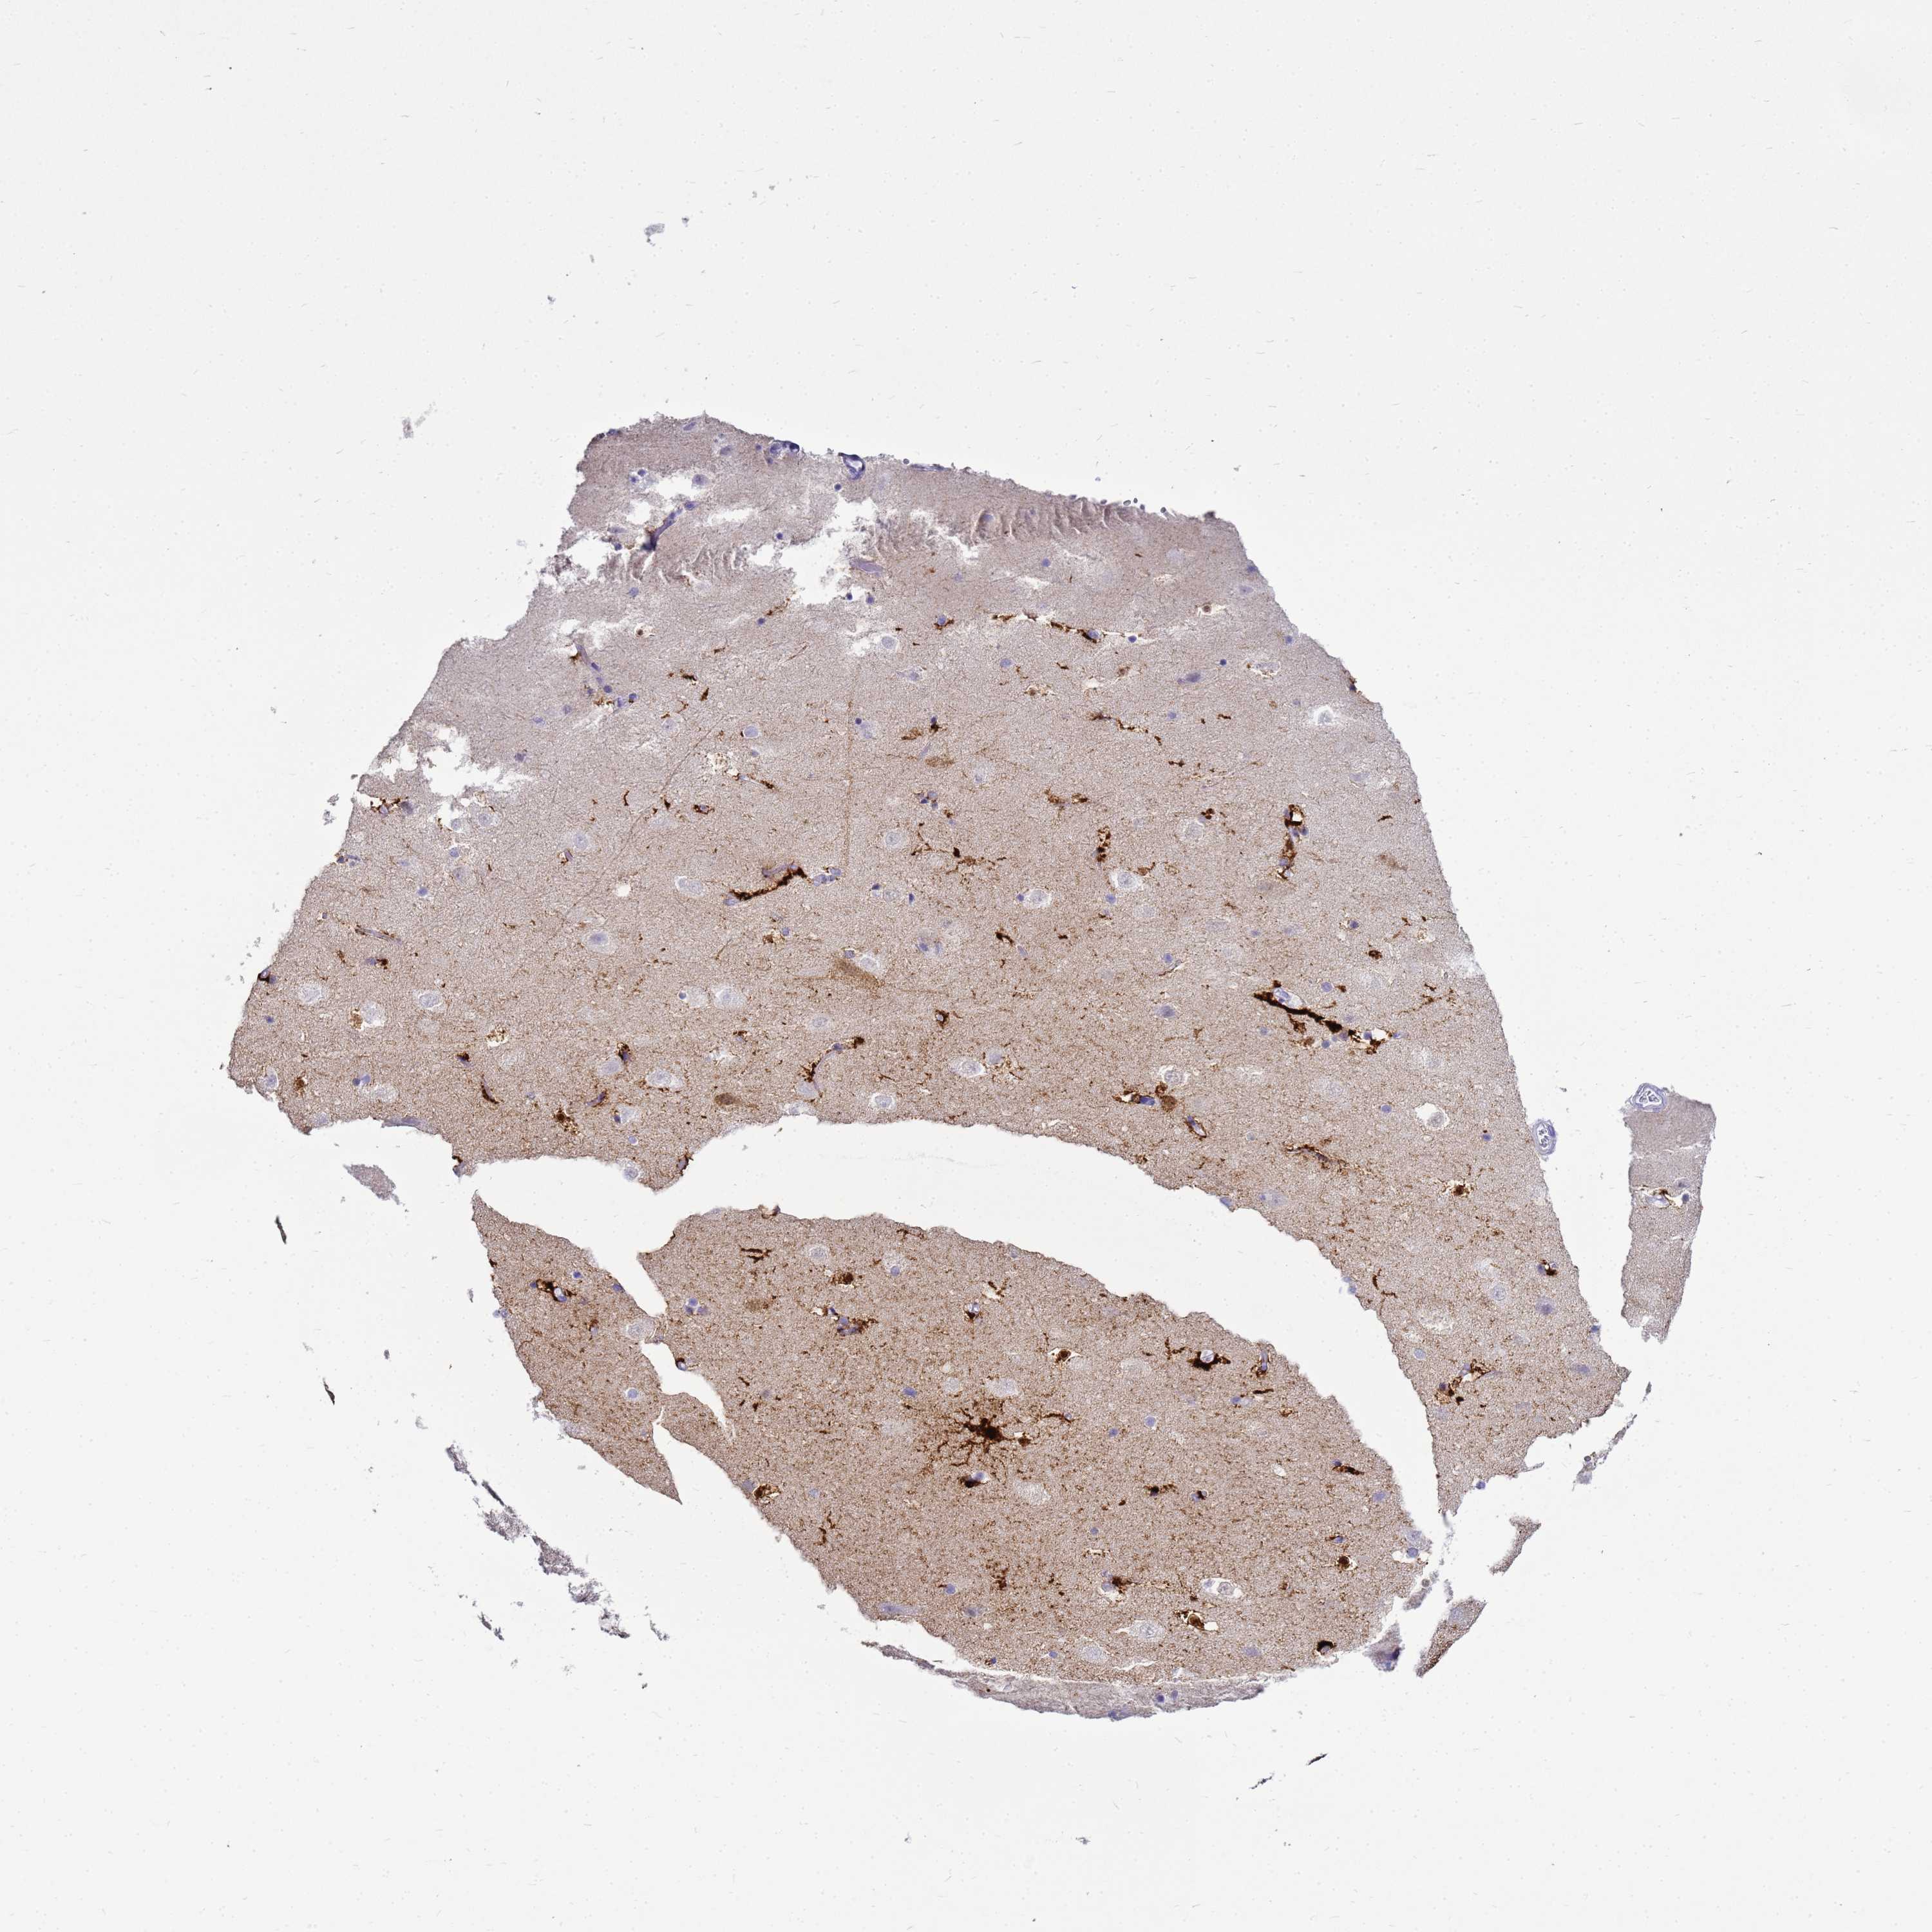

Antibody staining in the annotated cell types in the current human tissue is reported as not detected, low, medium, or high. This score is based on the staining intensity and fraction of stained cells.